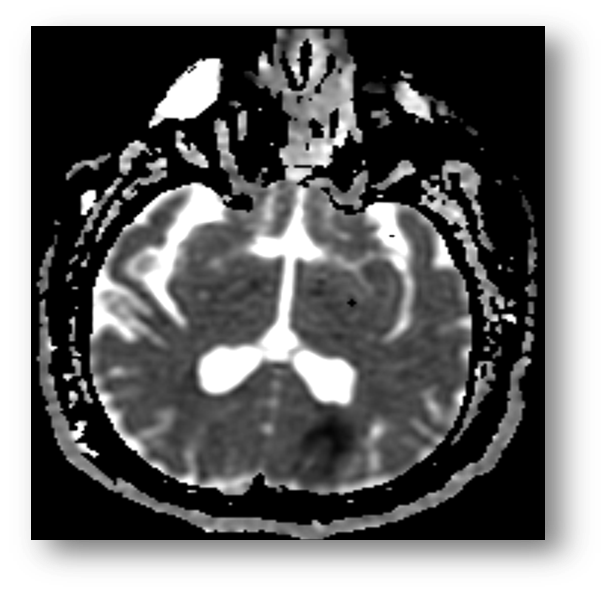

Refer to caption

Figure 3: T2 FLAIR showing hyperintense signal in the PCA and MCA distributions, consistent with acute ischemic stroke. Note that the hypointensity of cerebrospinal fluid due to fluid-attenuation allows for better contrast with the periventricular lesion.

Fluid attenuated inversion recovery (FLAIR) is useful in the diagnosis of certain pathologies such as periventricular white-matter lesion in multiple sclerosis. FLAIR can be T1 or T2 weighted. Figure (2) shows a sagittal section of a T1 FLAIR brain image, and Figure (3) shows a T2 FLAIR brain image.